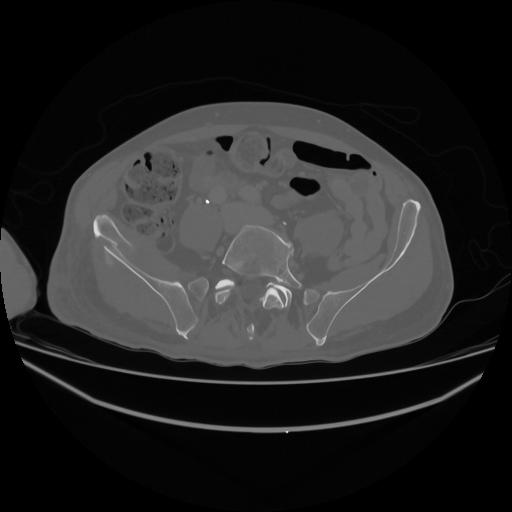

5 CUERPO,CE,Vol,1.0,CUERPO,,